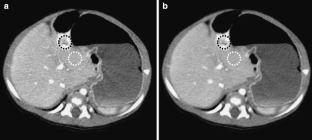

Fig 2.